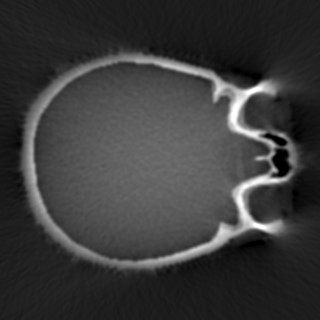

Cone-beam CT (CBCT) employs a flat-panel detector to achieve three-dimensional imaging with high spatial resolution. However, CBCT is susceptible to scatter during data acquisition, which introduces CT value bias and reduced tissue contrast in the reconstructed images, ultimately degrading diagnostic accuracy. To address this issue, we propose a deep learning-based scatter artifact correction method inspired by physical prior knowledge. Leveraging the fact that the observed point scatter probability density distribution exhibits rotational symmetry in the projection domain. The method uses Gaussian Radial Basis Functions (RBF) to model the point scatter function and embeds it into the Kolmogorov-Arnold Networks (KAN) layer, which provides efficient nonlinear mapping capabilities for learning high-dimensional scatter features. By incorporating the physical characteristics of the scattered photon distribution together with the complex function mapping capacity of KAN, the model improves its ability to accurately represent scatter. The effectiveness of the method is validated through both synthetic and real-scan experiments. Experimental results show that the model can effectively correct the scatter artifacts in the reconstructed images and is superior to the current methods in terms of quantitative metrics.